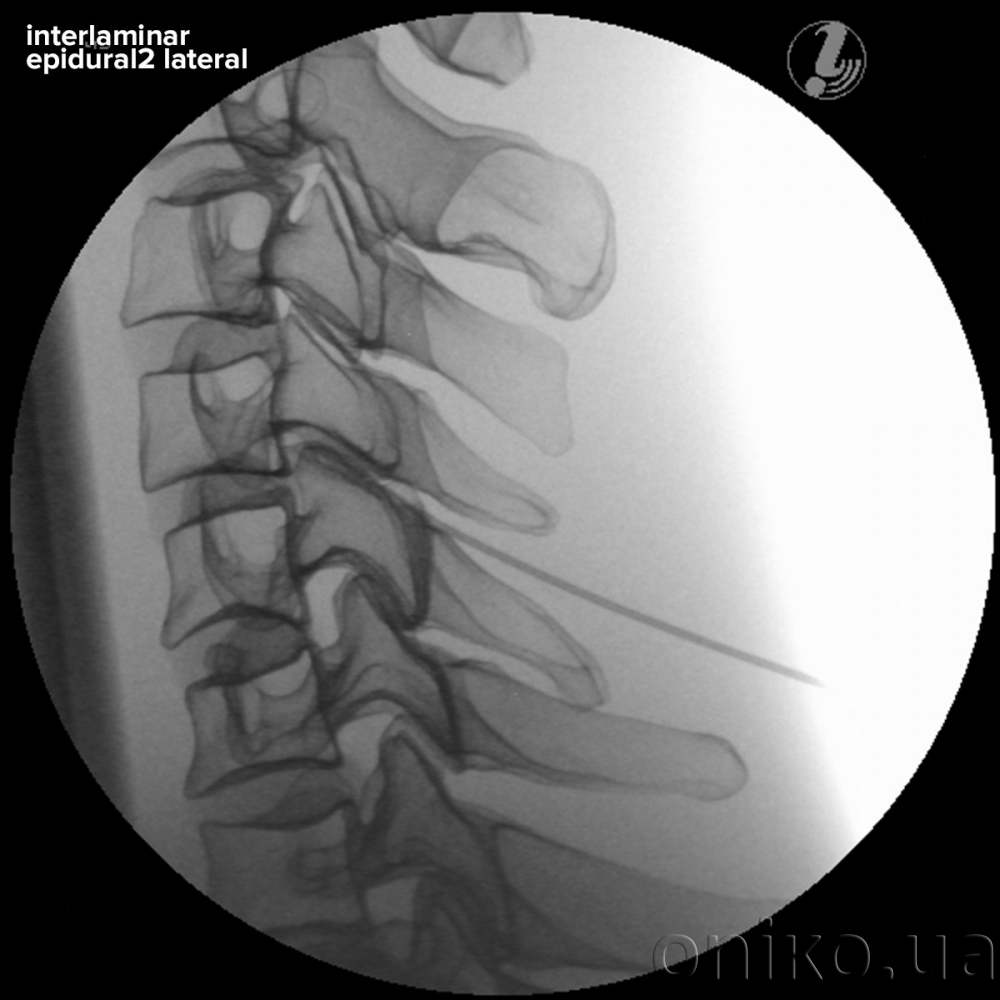

• Interlaminar Epidural Injection

• Life-like radiopacity for realistic x-Ray images

• Anatomically accurate bone structure